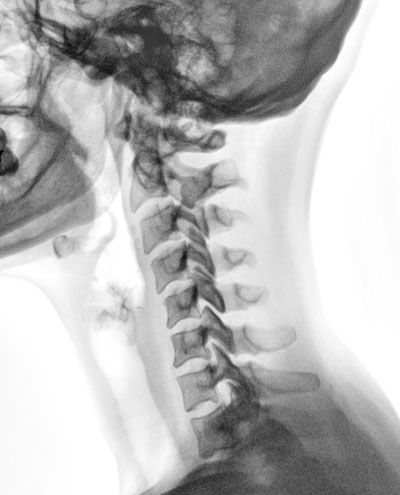

Scanner ou IRM, est-ce la même chose ? Publié le 23/05/2011, mis à jour le 24/05/2011 par SFR Scanner et IRM ont un certain nombre de points communs importants. Ils ont également des différences fondamentales à l’origine d’indications spécifiques selon l’âge du patient, la région anatomique explorée ou la pathologie recherchée. Dans les deux cas le patient est installé dans un tunnel mais celui de l’IRM est beaucoup plus long, pouvant entrainer une gêne chez les patients claustrophobes. La durée de l’examen est également plus longue en IRM (environ 30 minutes), qu’en scanner (autour de 5-10 minutes). Dans les deux cas, les images sont acquises en coupes, à partir desquelles de nombreuses reconstructions peuvent être réalisées en deux ou trois dimensions, dans tous les plans de l’espace. Les deux modalités suivent le même déroulement : un temps d’acquisition réalisé par le manipulateur suivant des protocoles très stricts élaborés par la Société Française de Radiologie, un temps de travail de l’image : mesure de la densité en scanner ou du signal en IRM, reconstruction multiplan, quantification de sténoses… et, surtout, un temps d’interprétation réalisé par le radiologue recherchant et analysant les anomalies et les intégrant dans le contexte clinique pour proposer une ou des hypothèses diagnostiques ; scanner et IRM nécessitent souvent l’utilisation de produits de contraste injectés par voie veineuse qui circulent dans les vaisseaux puis dans les parenchymes ; ces produits de contraste permettent, par exemple, de diagnostiquer un rétrécissement ou une obstruction d’un vaisseau ou de mieux détecter et caractériser des tumeurs. Les données acquises en scanner comme en IRM sont des données numériques, transmissibles et archivées. Cela permet ainsi de comparer les examens, ce qui est indispensable, de revoir les images à la lueur de nouveaux éléments ou encore de bénéficier de l’avis d’un radiologue expert dans tel ou tel domaine très spécifique. Enfin, le scanner et l’IRM sont des équipements d’imagerie dont l’installation est soumise à autorisation de la part des pouvoirs publics, des équipements donc contingentés, ce qui peut expliquer des délais de rendez-vous trop longs pour une prise en charge optimale ; c’est particulièrement vrai en IRM pour laquelle le parc existant évalué en nombre de machines/100000 habitants nous classe dans les très mauvais élèves européens avec un taux de 8,7 IRM/100000 habitants versus 15,6 pour la moyenne européenne. Si les points communs entre scanner et IRM sont nombreux, leur principe physique est totalement différent : le scanner repose sur une absorption spécifique des rayons X par les différents tissus. Il entraine une exposition aux rayons X et son indication doit être réfléchie, en particulier chez les femmes enceintes, chez les enfants et les sujets jeunes. Le scanner a une excellente résolution spatiale et permet de visualiser des structures inframillimétriques. L’IRM, quant à elle, repose sur la propriété que possèdent certains noyaux atomiques, d’émettre des signaux détectables quand ils sont placés dans un champ magnétique et soumis à une radiofréquence particulière, capable de les faire résonner. L’examen est interdit aux personnes porteuses d’un stimulateur cardiaque ou de corps étrangers intraoculaires. L’IRM a une excellente résolution en contraste et permet de mieux différencier des tissus de composition différente, c’est donc l’imagerie privilégiée dans l’étude des parenchymes, cérébral en premier lieu, mais aussi hépatique, mammaire ou prostatique. L’IRM permet une approche non seulement anatomique mais aussi fonctionnelle des différents organes et, de ce fait, de diagnostiquer une ischémie cérébrale de façon très précoce, seule façon de la rendre curable, ou bien d’approcher la composition biochimique d’une tumeur. En revanche, elle nécessite autour du patient un matériel (tube de perfusion, respirateur …) insensible au champ magnétique. Cela explique que le scanner soit systématiquement préféré à l’IRM dans certaines situations : en urgence en dehors de l’imagerie du cerveau, chez les patients de réanimation ou dans la réalisation de gestes guidés par l’imagerie qu’ils soient diagnostiques ou thérapeutiques. Scanner et IRM sont certainement les modalités d’imagerie qui ont bénéficié des plus grands progrès technologiques ces dix dernières années avec le développement de nouveaux champs d’application comme l’imagerie du cœur et des coronaires et plutôt que de les opposer, il faut les considérer comme complémentaires ainsi qu’en témoigne l’imagerie de fusion, promise à un grand développement, car elle permettra de fusionner les renseignements donnés par scanner et IRM. Pr Patrice TAOUREL Responsable de la communication de la SFR